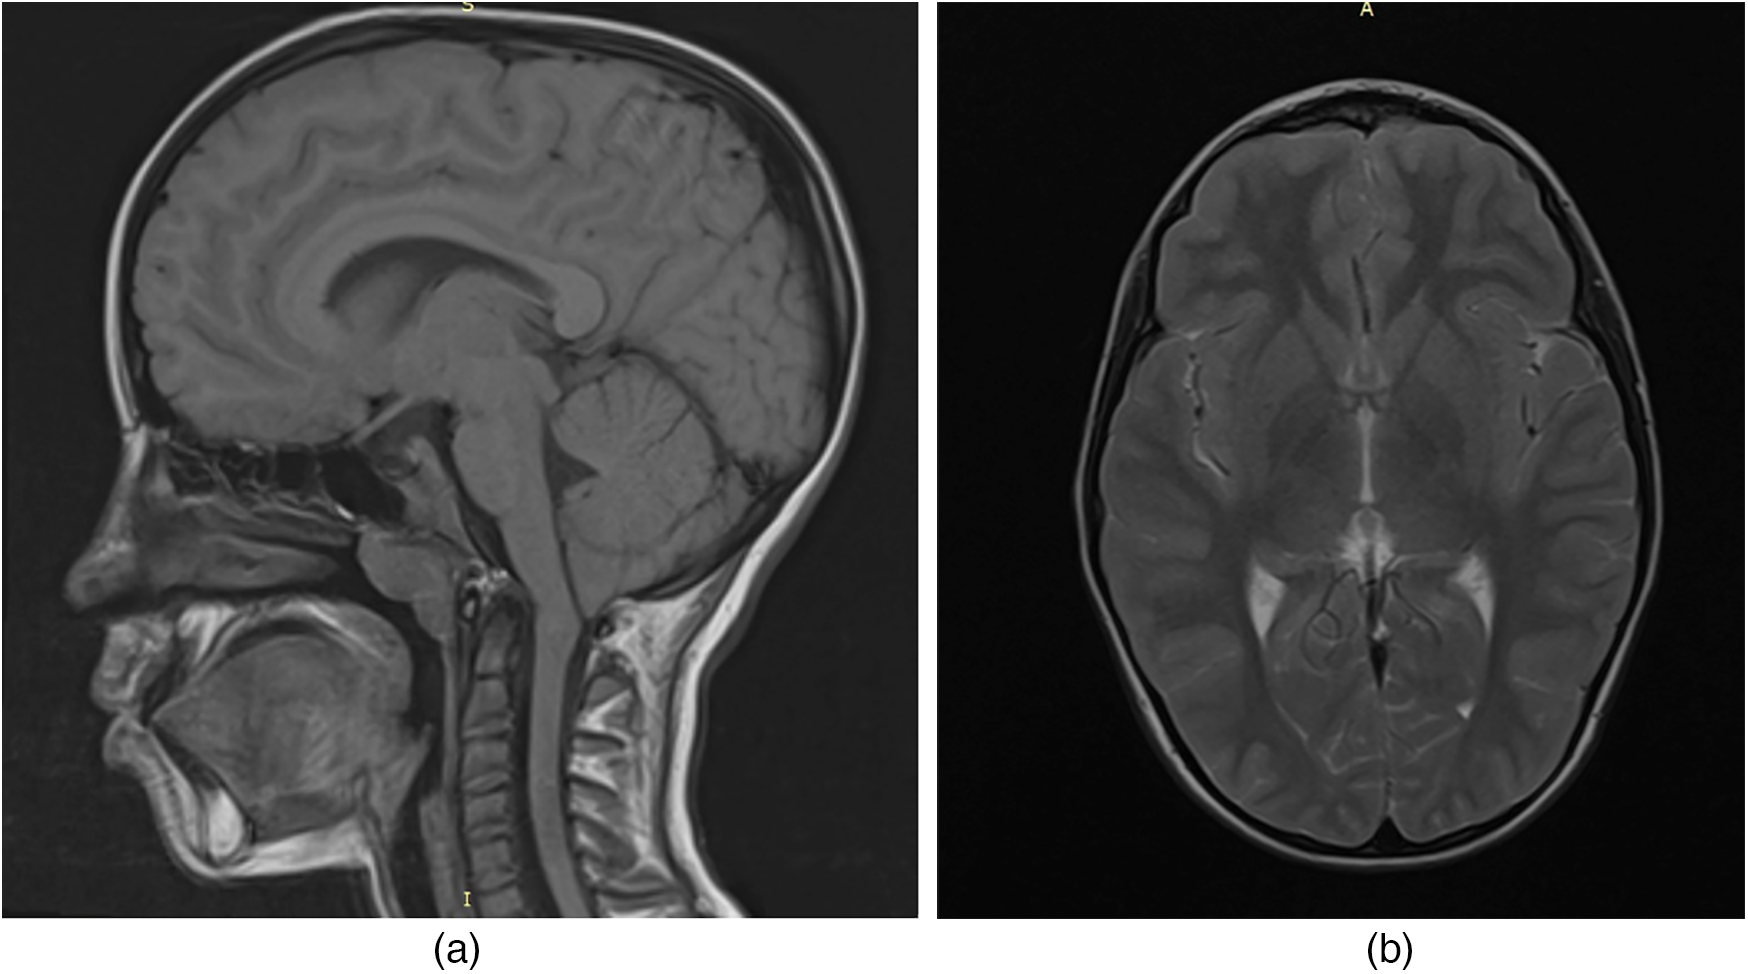

To evaluate for potential central nervous system involvement, brain magnetic resonance imaging (MRI) was performed. The imaging revealed a caudal displacement of the cerebellar tonsils extending 7 mm below the foramen magnum (Figure 1), consistent with a diagnosis of Arnold-Chiari type I malformation, which was subsequently confirmed by a neurosurgical evaluation.

Figure 1. MRI of the child's brain with acid sphingomyelinase deficiency (ASMD) type A/B disease and Arnold-Chiari I malfunction: (a) MRI section in the sagittal plane; (b) MRI section in the axial plane.

In our patient, brain MRI revealed a 7 mm caudal descent of the cerebellar tonsils below the foramen magnum, consistent with Arnold Chiari malformation type I (CM-I). This form of Chiari malformation is characterized by isolated downward herniation of the cerebellar tonsils of ≥5 mm in the absence of brainstem displacement or myelomeningocele, distinguishing it from more severe forms such as type II. CM-I is often asymptomatic but can present with neurological signs including ataxia, nystagmus, vertigo, dysmetria, or headaches due to impaired cerebrospinal fluid (CSF) flow and compression of posterior fossa structures (19).

In our case, the presence of cerebellar signs, mild dysmetria, ataxia, and adiadochokinesia were observed without the characteristic CNS imaging findings typical of ASMD. These signs were therefore attributed to CM-I.